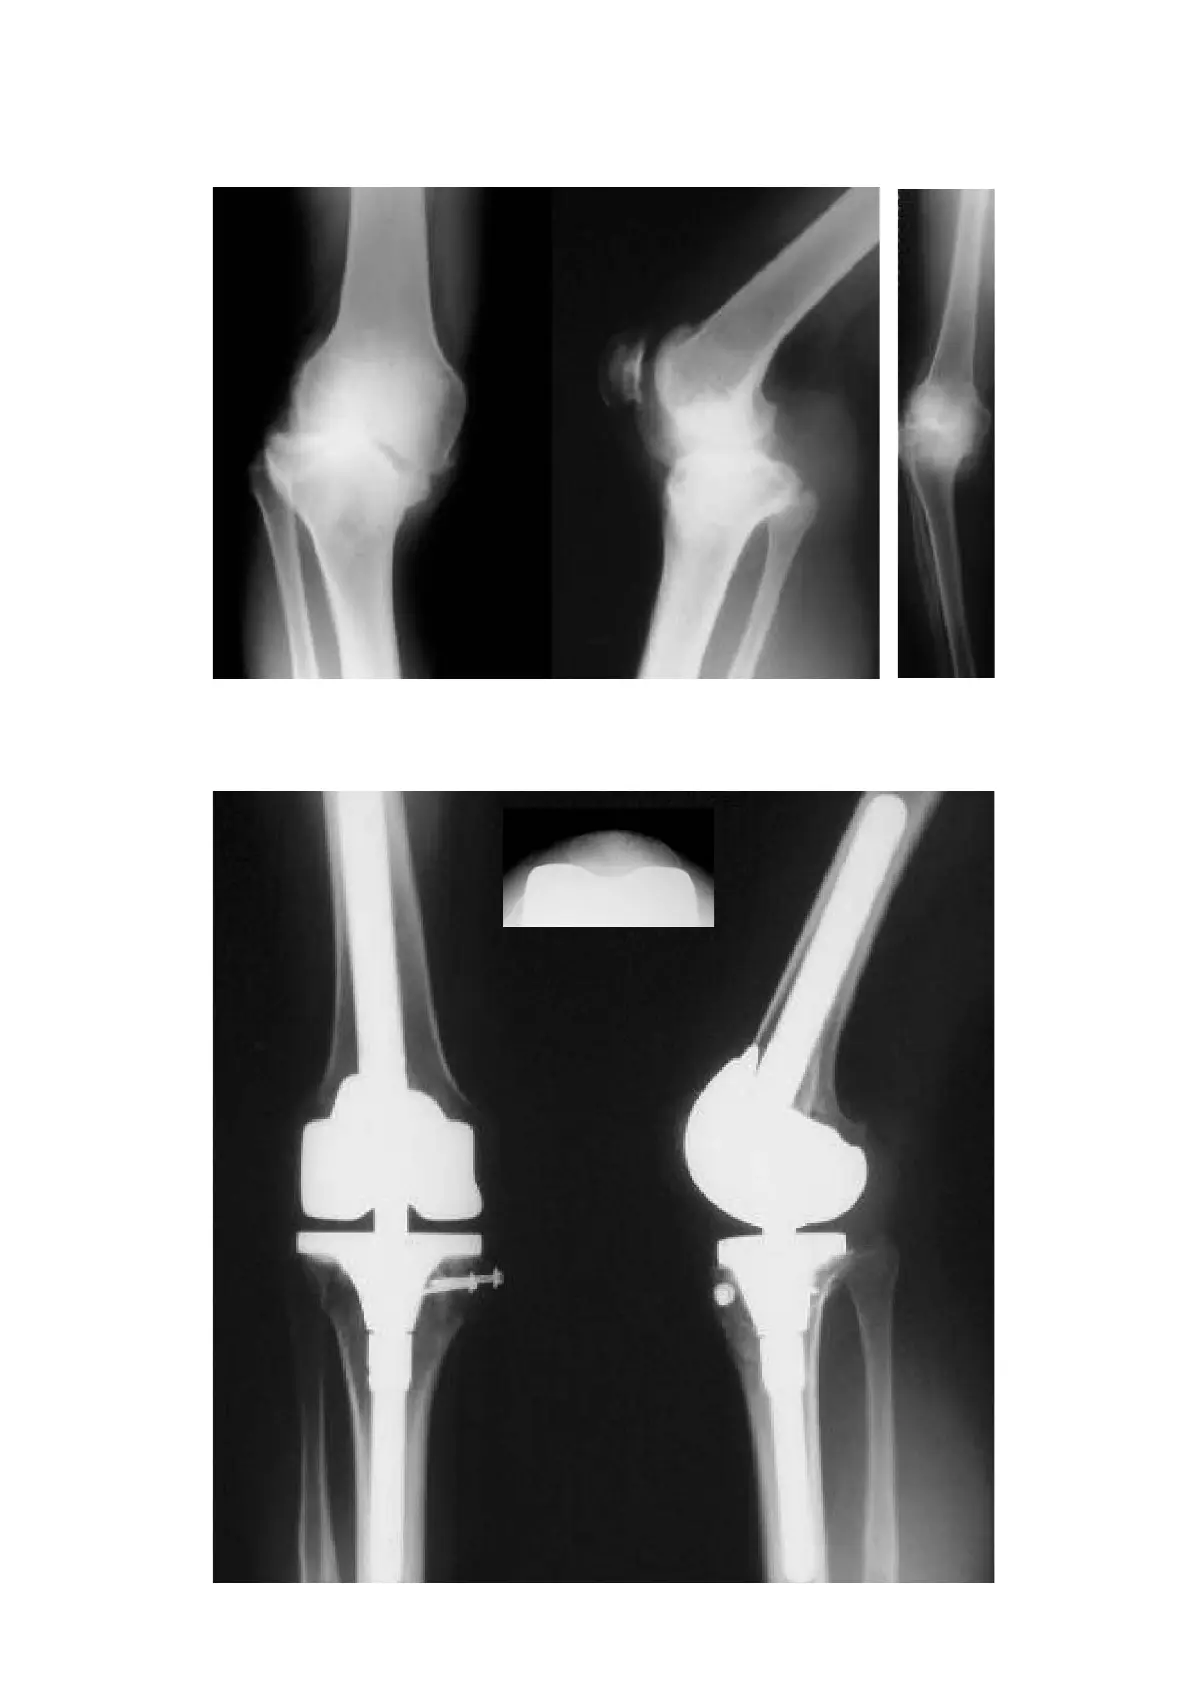

Preoperative situation

Patient with severe joint instability (varus gonarthrosis) as well as medial joint destruction.

Postoperative result

Immediately postoperative; functional and pain-free reconstruction with RT-PLUS™ Modular knee.